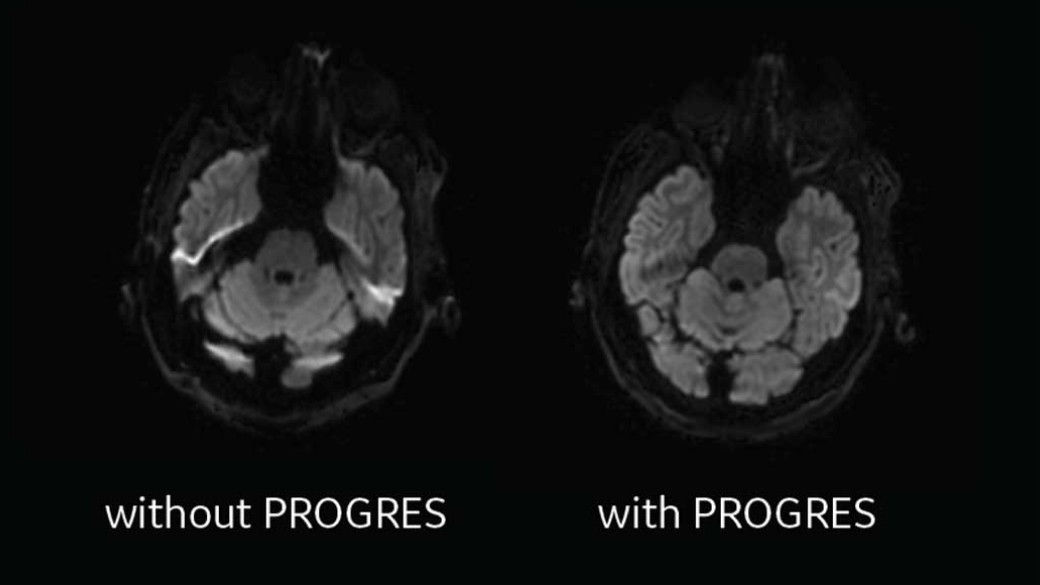

Real-time applications provide motion-correction and distortion artifact reduction during the scan

progres-desktop